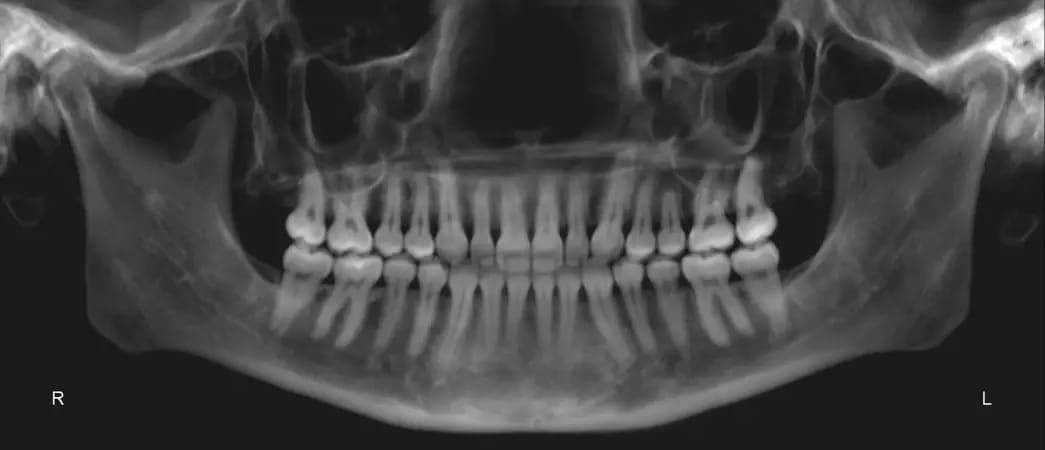

Панорамная рентгенограмма подтвердила наличие всех четырех зачатков третьих моляров. Примечательно, что в верхней челюсти наблюдалась выраженная резорбция корней, хотя общее состояние пародонта казалось хорошим (фото 3). Цефалометрический анализ показал тип скелета II класса, тенденцию к вертикальному росту и заднюю ротацию нижней челюсти. Было обнаружено, что резцы верхней и нижней челюсти слегка наклонены (фото 4).

Фото 3: Дооперационная панорамная рентгенограмма.